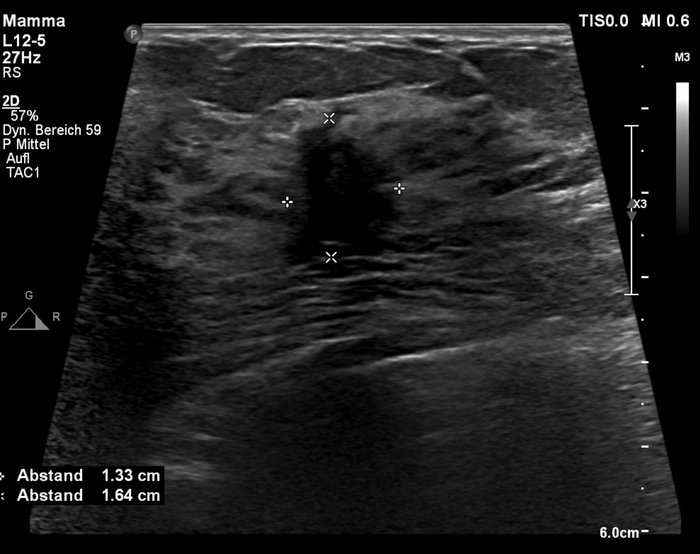

Сразу после маммографии провели ультразвуковое обследование, где очаг хорошо определялся как сильно гипоэхогенная область (мало отражающая УЗ лучи) с нечёткими контурами и ориентировкой перпендикулярно плоскости кожи: